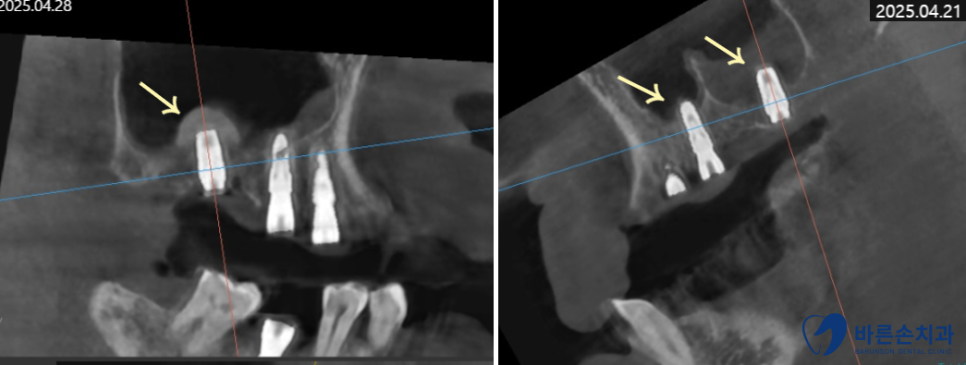

촬영일 2025.04.21/28

양쪽 위 어금니 총 3개 부위에 상악동 거상술을 진행하고

임플란트를 잘 식립했습니다.